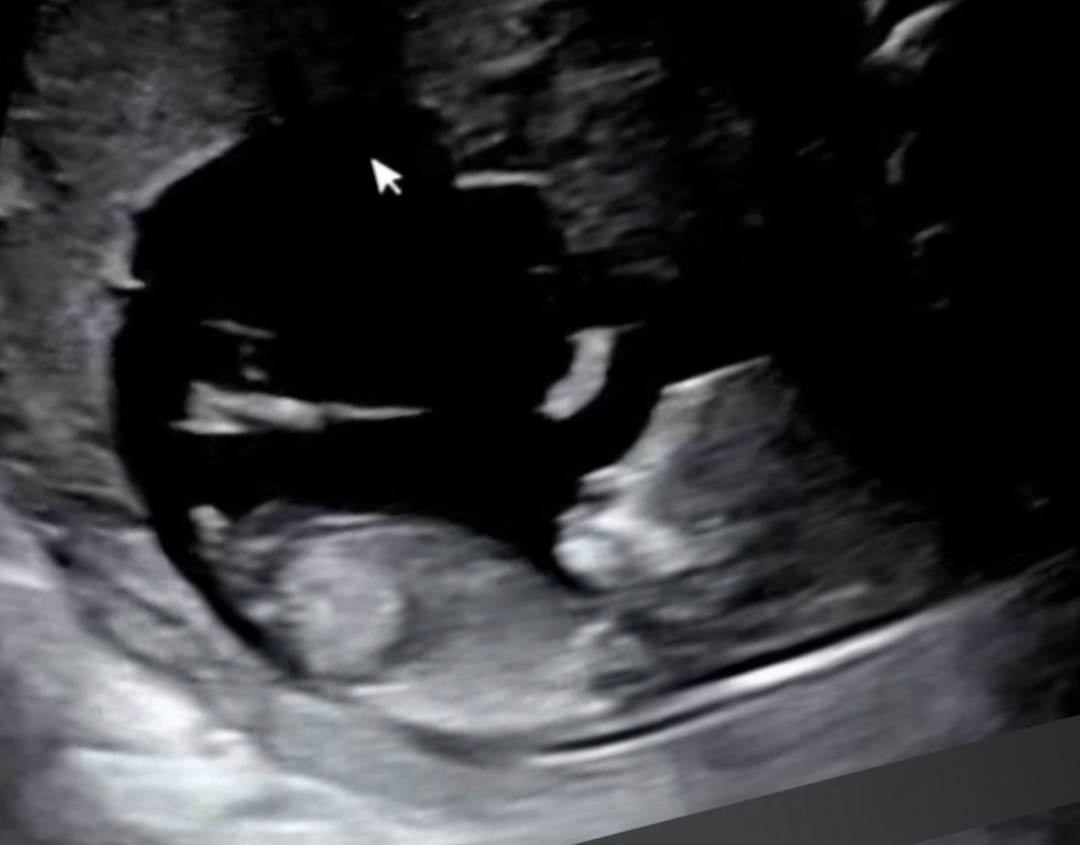

12주 각도법 봐주세요!! 궁금합니다!!

아들일까요 딸일까요?!!

남아같아 보여요!